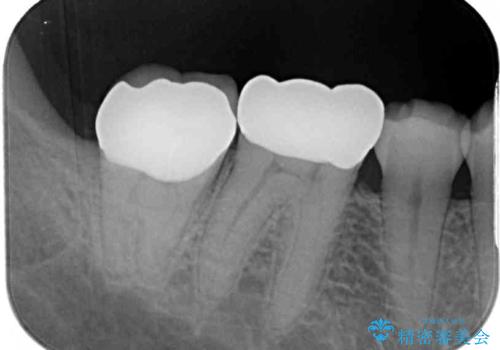

レントゲン写真から、神経の近くにまでむし歯が及んでいる様子が分かり、範囲も広範囲であったので、まずは仮歯に置き換え、その後オールセラミッククラウンにて補綴治療を行うこととしました。

虫歯は歯髄組織のギリギリにまで及んでいたものの、歯髄組織が露出することはなく、処置から数日経った日に行った検査でも歯髄組織の異常所見は認めれらませんでした。

速やかに補綴治療を行い、無事に海外赴任前に治療を終えることができました。